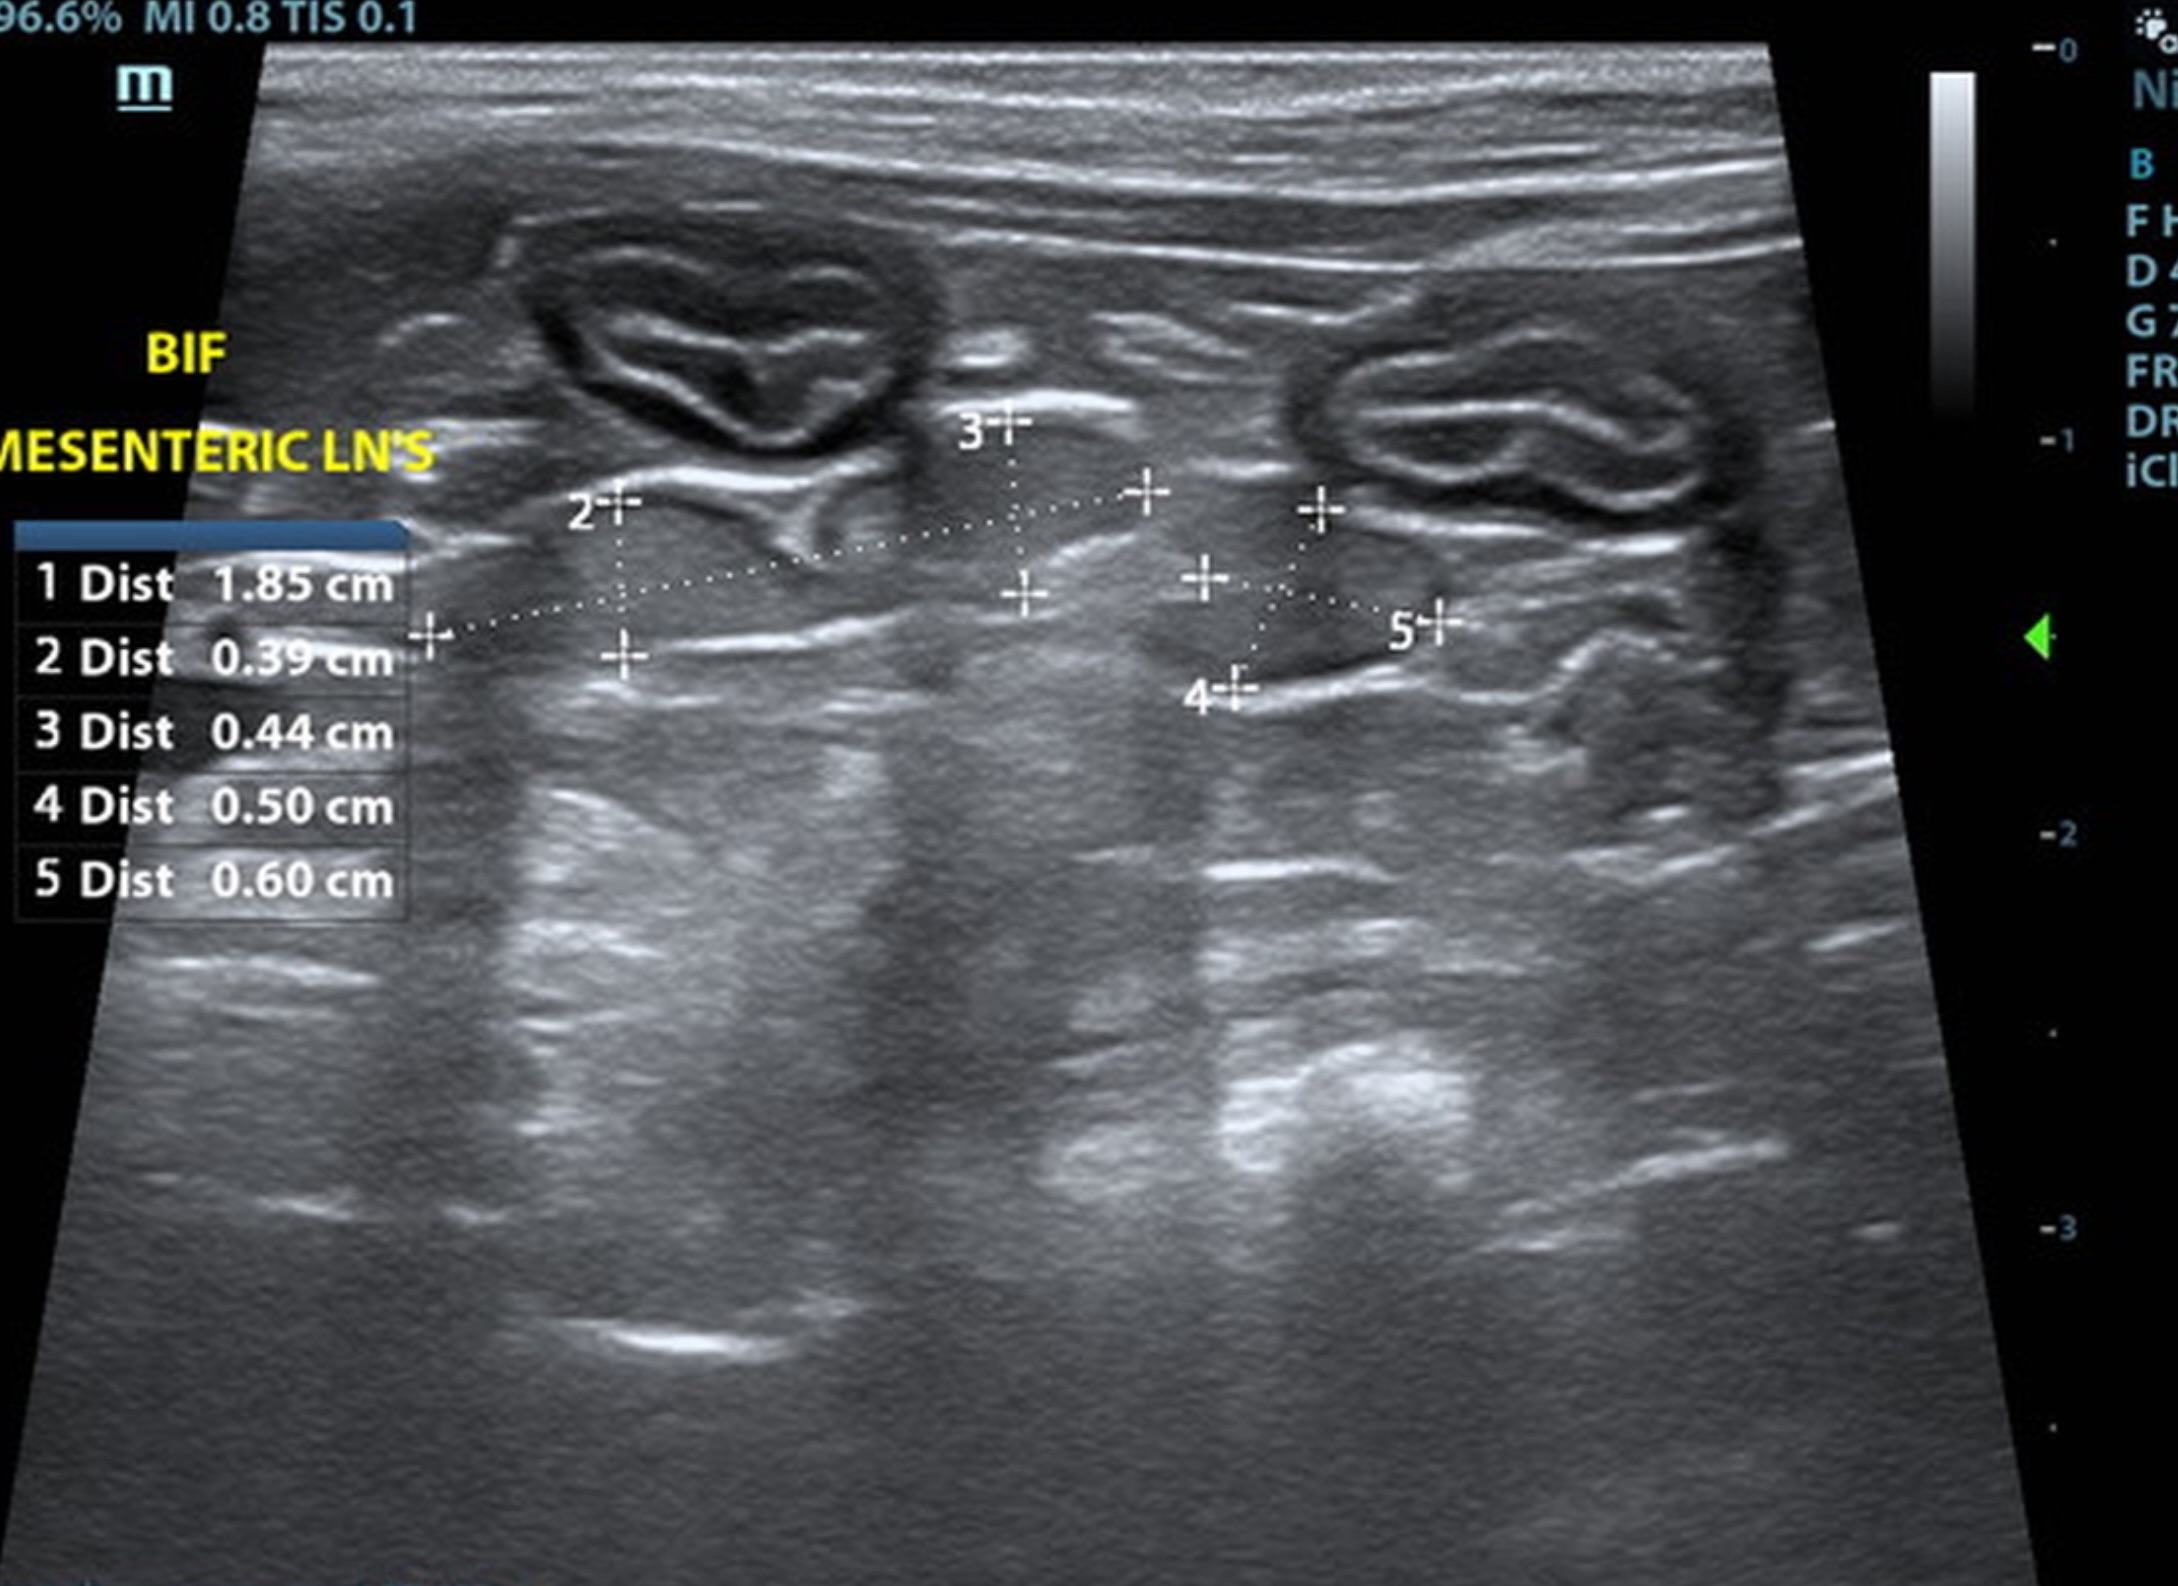

Mild uniform prominence of the gastric mucosa as well as areas of “ropey” small intestinal wall. Hypertrophied mscularis with inverted normal ratio (1:3). Submucosa slightly irregular, thickened and hyperechoic suggestive of low grade chronic inflammation. Probable IBD with low possibility of early neoplastic event such as lymphoma or less likely dry form FIP. Consider full thickness biopsies via open lapartotomy. Reactive mesenteric lymph nodes measured 1.85 x 0.44.